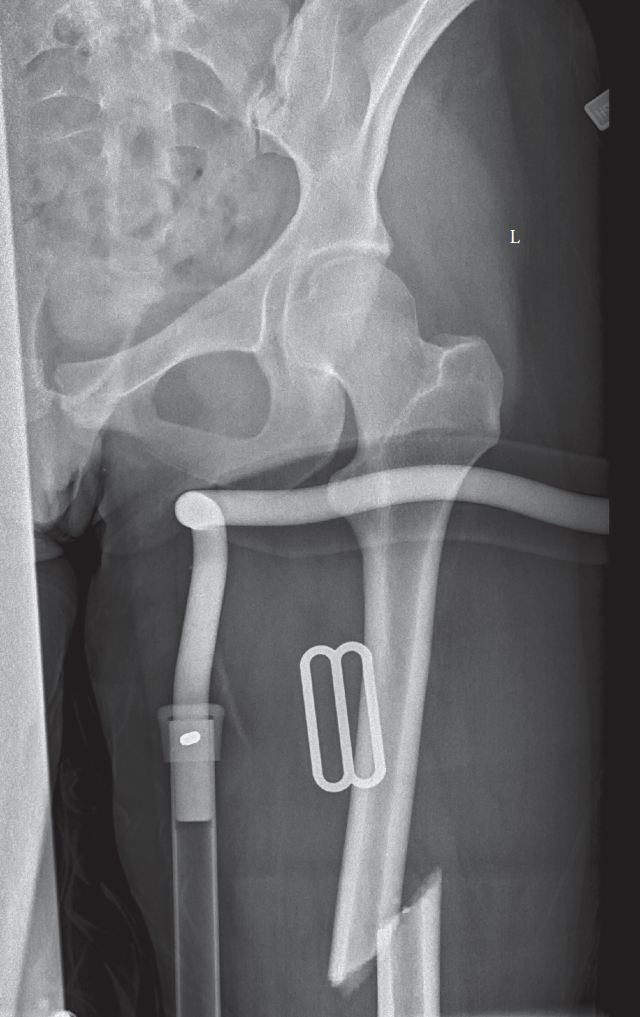

Figure 1: Intraoperative fluoroscopic image demonstrating antegrade intramedullary nailing. Note the guide wire across the fracture, reaming reamer inside the canal, and planned nail path. Proper alignment and central guide wire placement are critical for successful reduction and fixation.